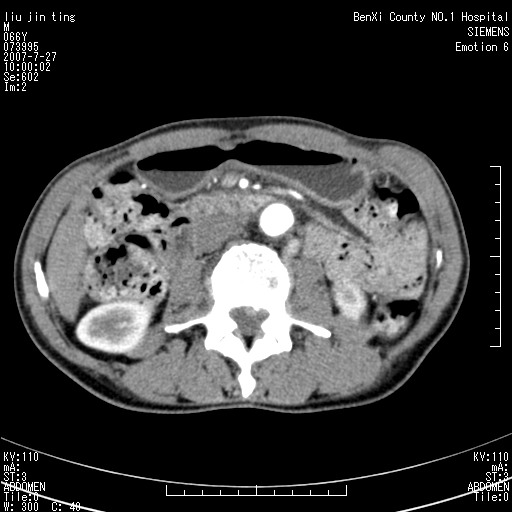

腹痛,背痛,无恶心呕吐,不黄,彩超示胰腺钩癌,ct扫描病灶平扫30-40hu,增强后动脉期40--60hu,静脉期50-68hu,真的是钩突上的么?您要试一试么?

动脉期

沿着肠系膜上动脉呈匍匐性生长的软组织肿块,形态不规则,包绕肠系膜上动脉,呈明显强化,考虑来源于肠系膜的恶性肿瘤

沿着肠系膜上动脉呈匍匐性生长的软组织肿块,形态不规则,包绕肠系膜上动脉,呈轻-中度强化,考虑来源于肠系膜的恶性肿瘤。

钩突是正常的,只见腹膜后淋巴结的肿大,考虑淋巴瘤或转移可能。